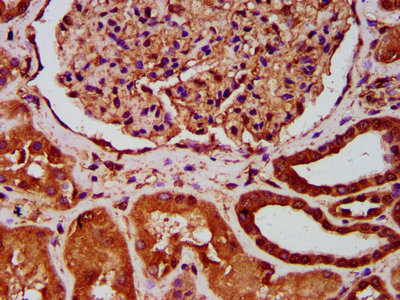

• IHC image of CSB-PA002468LA01HU diluted at 1:400 and staining in paraffin-embedded human kidney tissue performed on a Leica BondTM system. After dewaxing and hydration, antigen retrieval was mediated by high pressure in a citrate buffer (pH 6.0). Section was blocked with 10% normal goat serum 30min at RT. Then primary antibody (1% BSA) was incubated at 4°C overnight. The primary is detected by a biotinylated secondary antibody and visualized using an HRP conjugated SP system.